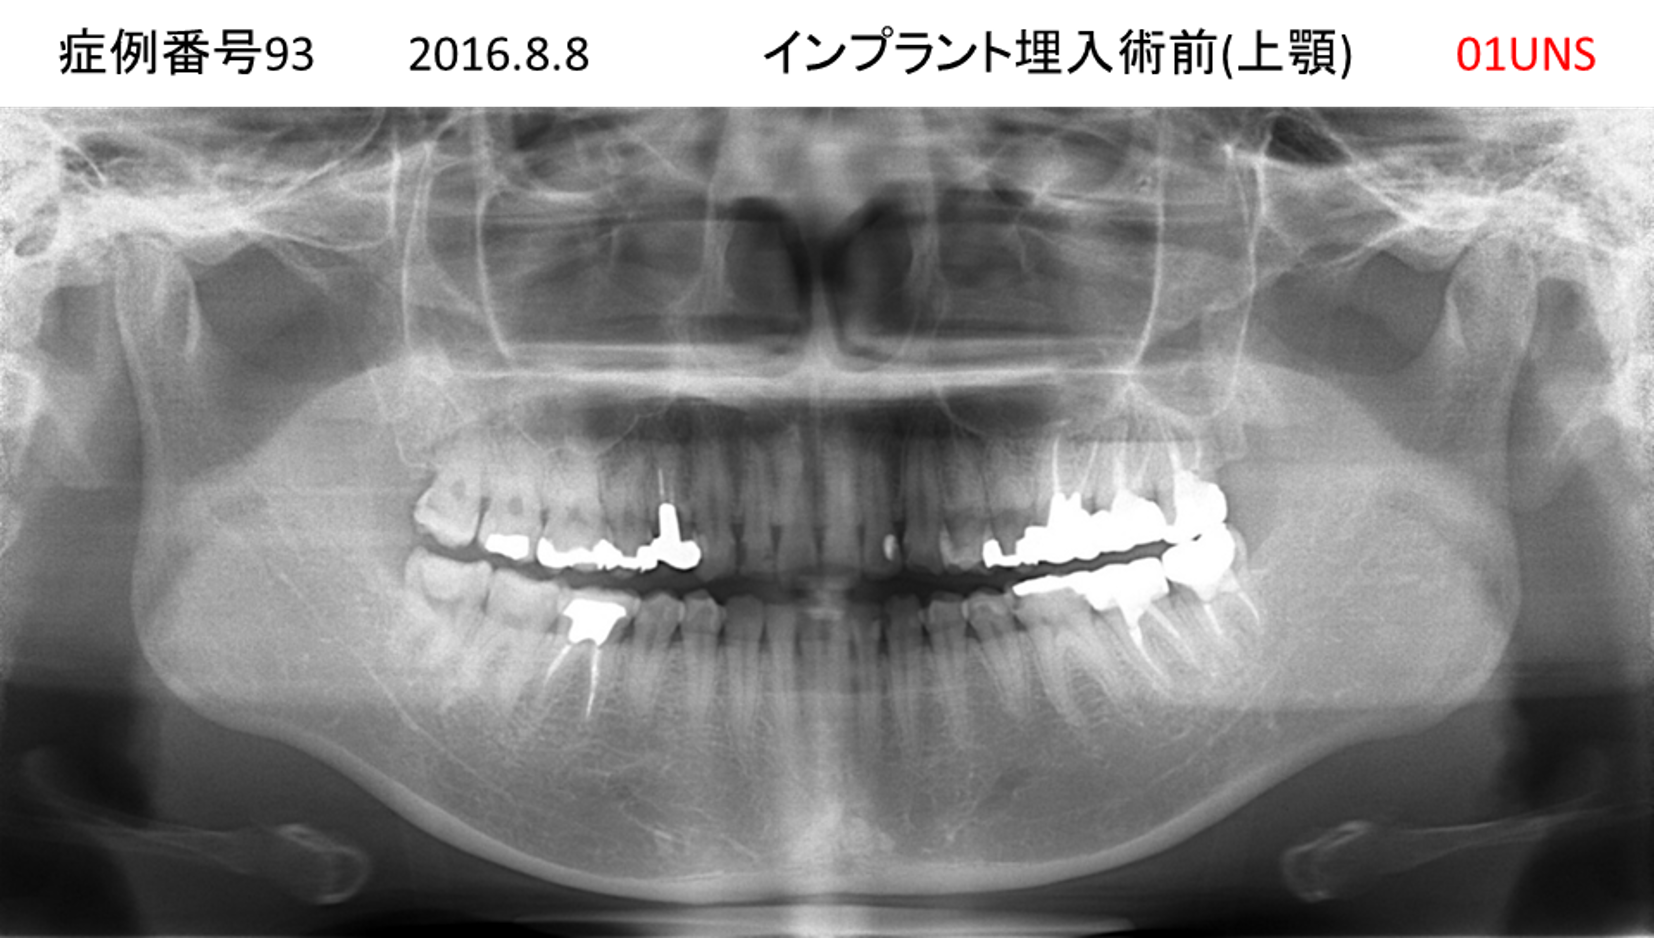

かめない/上の歯が揺れてきた患者様のインプラント症例

| 治療名称 |

インプラント |

| 治療費用 |

390万円+税 |

| 治療期間 |

6か月 |

| 患者さんの症状(主訴) |

かめない。上の歯が揺れてきた。 |

| 治療内容 |

サイナスリフト、抜歯即時インプラント |

| 治療結果 |

上の歯の揺れが収まった。噛めるようになった。食事がおいしい。 |

| 治療の注意点(リスク/副作用) |

インプラントが壊れたら再治療が必要 |